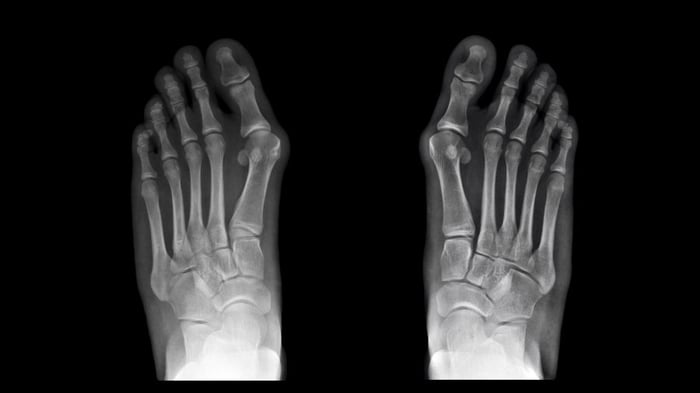

Il ruolo dell'imaging per la diagnosi di alluce valgo

L'imaging serve per studiare in dettaglio la deformità dell’alluce valgo e comprendere quale sia la cura più appropriata, se conservativa o chirurgica, sulla base dell'evolutività. Può includere:

- Esame di indagine base: Una radiografia dei piedi in carico, meglio se bilaterale. È fondamentale che le radiografie siano eseguite in carico (cioè stando in piedi) e che siano bilaterali. Questo permette di studiare l'anatomia del piede mentre lavora e di confrontare i due piedi, che spesso sono simili anche se solo uno fa male.